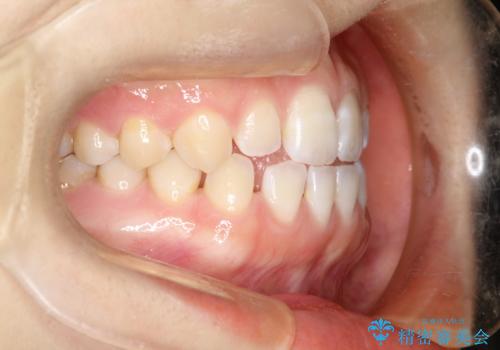

前歯の隙間を閉じたい インビザラインによる矯正

- 上下の前歯に隙間があるとのことで来院されました。

インビザラインにて隙間を閉じる矯正を行いました。